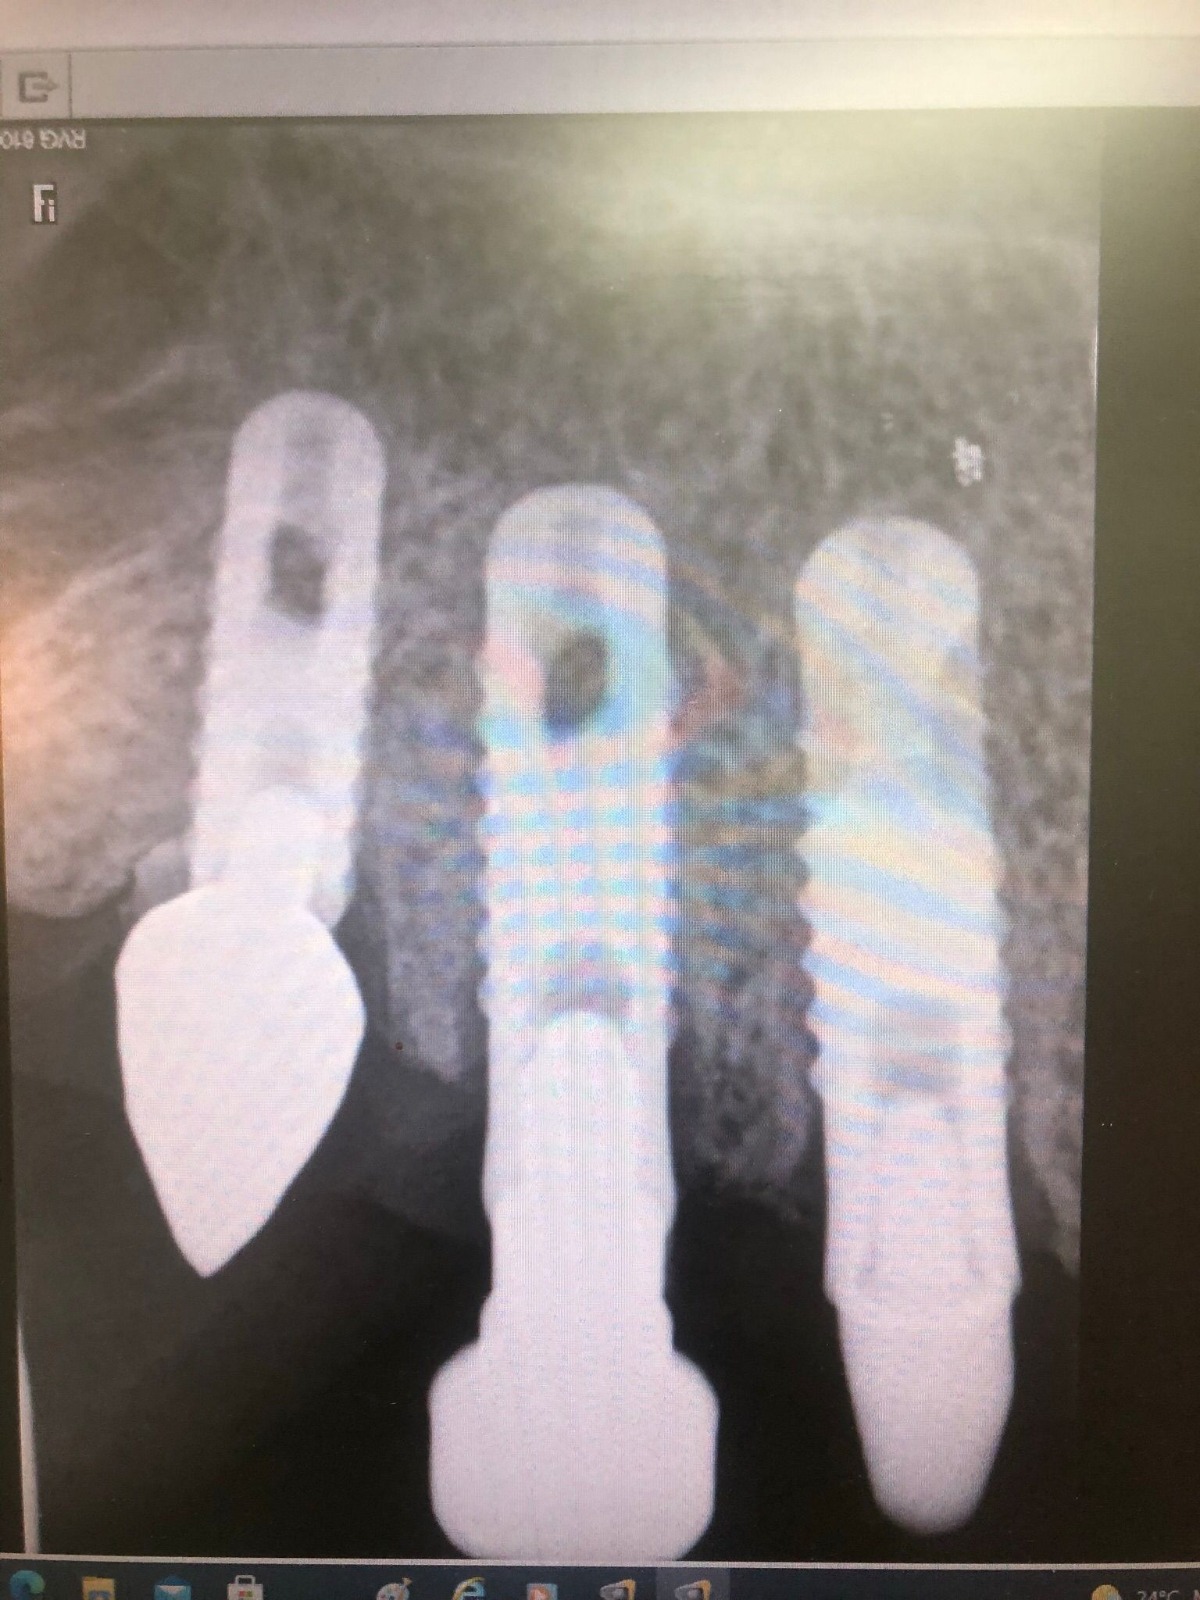

Actualmente vuelve el paciente de nuevo con la misma prótesis. Había roto dos de los tres pilares en concreto los más distales. El primero de los dos había roto la rosca del aditamento dentro del implante como ocurre habitualmente. Pero el ultimo pilar había roto directamente la cabeza del implante tal como se ve en la radiografía y lo que quedaba era un cilindro de titanio macizo perfectamente integrado en el maxilar, sin posibilidad de enroscar nada. Le explicamos al paciente que habría que quitar y poner un implante en el mismo acto. El paciente dijo que no, así que decimos que no se haría cirugía. Buscamos solución alternativa: hacemos un un agujero en el centro del macizo cilíndrico del implante roto y pasamos sucesivamente el set de machos roscantes. Utilizamos una fresa cañón de 1 mm que poco a poco se va introduciendo hasta 8mm con un poco de vagación, que hace que sea un poco mas de 1mm de diámetro. Posteriormente pasamos el conjunto de machos roscantes de métrica 2mm para poder usar un aditamento experimental, que era un palo de rosca de diámetro 2 mm unido a un cuerpo metálico en forma de sombrero napoleónico fabricado en cromo/cobalto, prototipos primitivos de la sistemática ASATIM y que tienen la característica de tener gran resistencia a la fractura. Nos llevó un tiempo largo el tallado de dichos aditamentos, tal como se puede observar en las imágenes, y tras cicatrizar la encía se le hizo una prótesis estándar. Esperemos que no lo rompa más veces.